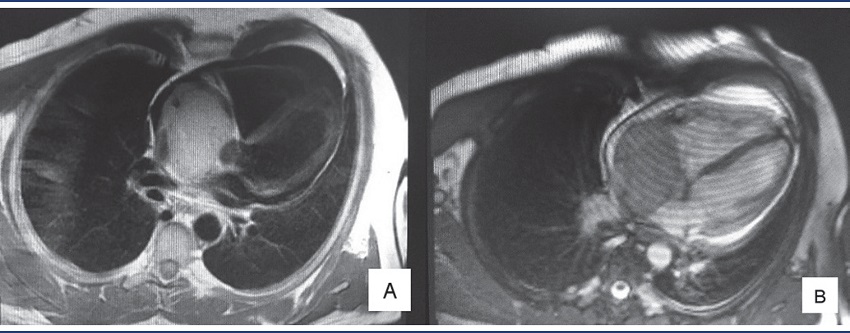

A 44-year-old male patient experienced fatigue and dyspnea during cycling. After a period, he evolved to a picture of swelling in the face and upper chest (superior vena cava syndrome). A chest radiograph was taken, which showed no alteration, and the recorded electrocardiogram showed sinus rhythm. Exercise stress test displayed no ischemic changes. Transthoracic echocardiography (TTE) showed left and right ventricles with preserved dimensions, thickness and contractility. Left and right atria presented normal dimensions, but, inside the right atrium, close to the entry of the superior vena cava, a pedunculated mass with irregular borders was visualized, measuring 52 × 43 mm, causing obstruction in the atrium. A nuclear magnetic resonance (NMR) revealed a large sessile immobile heterogeneous mass, measuring about 77 × 54 mm, situated in the interior of the right atrium, apparently infiltrating inferior and superior venae cavae and invading tricuspid valve, interatrial septum and pericardium (Figure 1). On T1-weighted sequences, the mass appeared to be hypodense; on T2, presented hypersignal. On fat-suppressed sequences, there was no signal dropout, suggesting the mass was not a lipoma. After contrast infusion, heterogeneous late enhancement was perceived, with sparse areas of hyposignal inside. Due to those findings, the diagnostic possibilities were angiosarcoma, lymphoma, myxoma and myxosarcoma.

NMR: nuclear magnetic resonance.